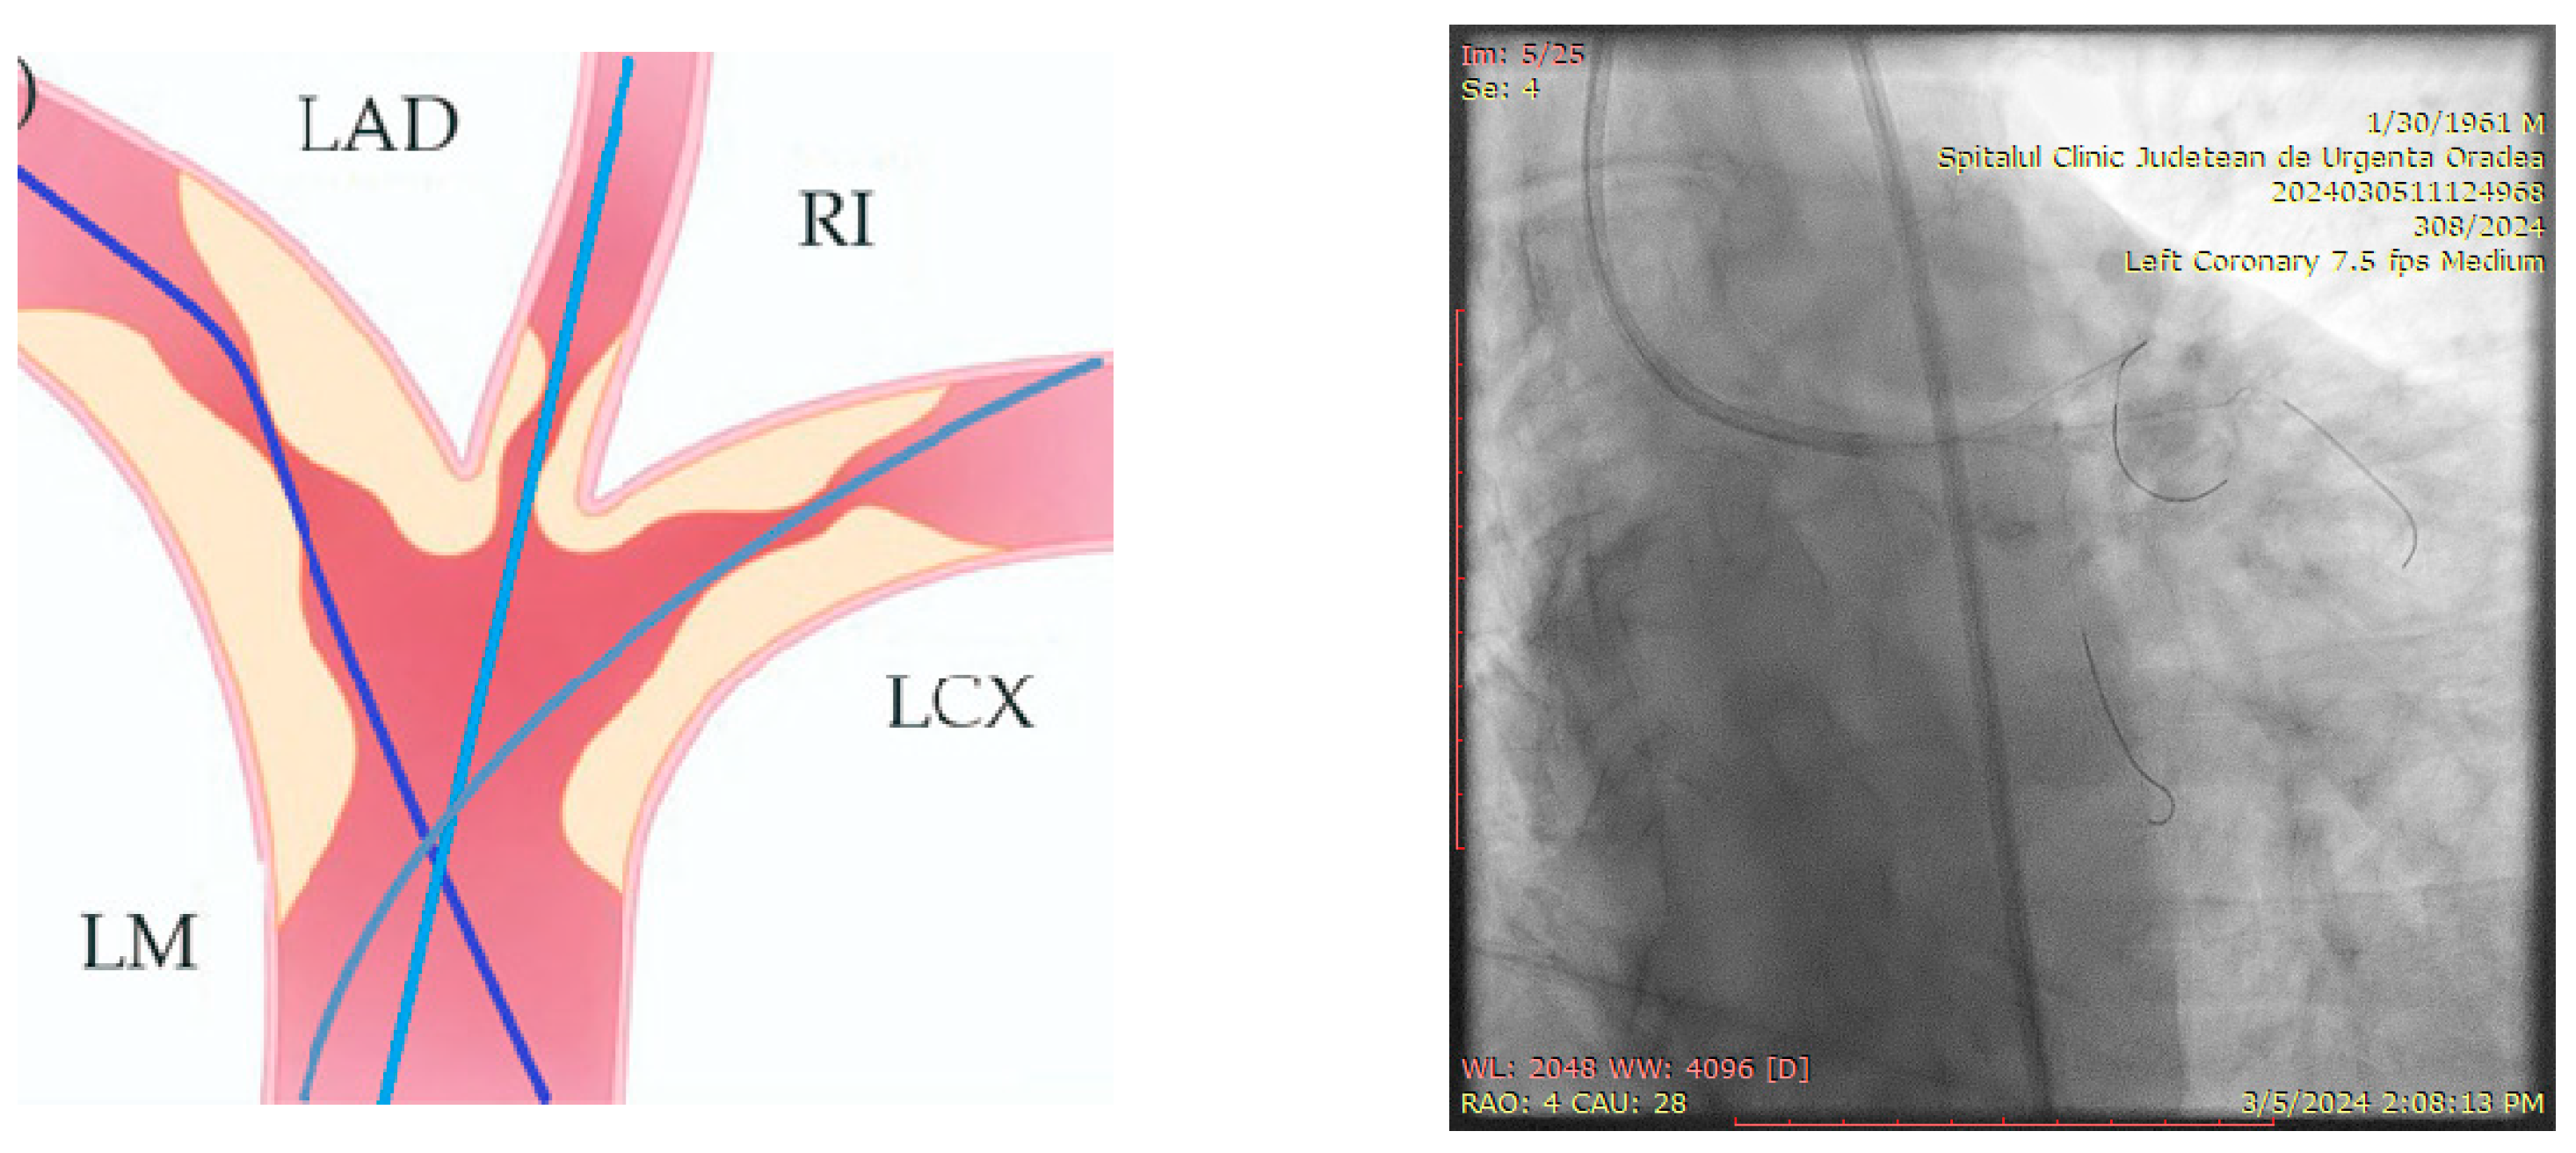

The ostium of left anterior descending artery (LAD) presented a 75% stenotic lesion, with the proximal segment displaying a 90% lesion (Figure 3). The left circumflex artery (LCX) revealed a 75% stenotic lesion of the ostium and tapered disease of its distal segment with areas of ectasic disease, with the ostium of the ramus intermedius (RI/RM) showing a 75% lesion (modified Medina classification 0-1-1-1 [4]) (Figure 4, Figure 5, Figure 6, Figure 7, Figure 8, Figure 9 and Figure 10).

Figure 3.

Left coronary artery (Right anterior oblique caudal (RAO) caudal view).

Figure 4.

Left coronary artery—LAD and LCX (LAO caudal). Red arrow and circle—ostium of LAD. Yellow arrow and square—ostium of LCX.

Figure 5.

Left coronary artery—RM(LAO caudal). Green arrow and square—ostium of RM.

Figure 6.

Left coronary artery (RAO cranial).

Figure 7.

Left coronary artery (LAO cranial).